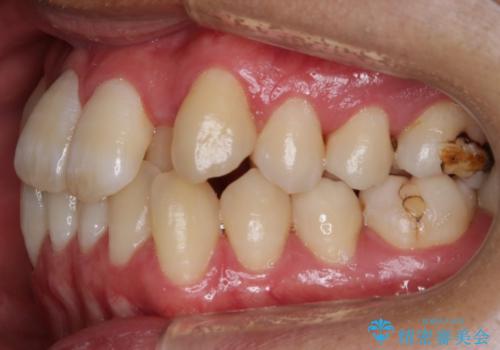

- 前歯のガタつきの治療を主訴にご来院されました。

目立たない装置をとのご要望があったため、検査結果をふまえてインビザラインでの非抜歯矯正を行うこととなりました。

非抜歯での治療

抜歯をせずに歯のガタつきを治すためのスペースを作るために

①歯の遠心移動

②歯列弓の拡大

③IPR(歯を少し小さく削る)

この3つの方法を複合的に組み合わせて治療を行いました。